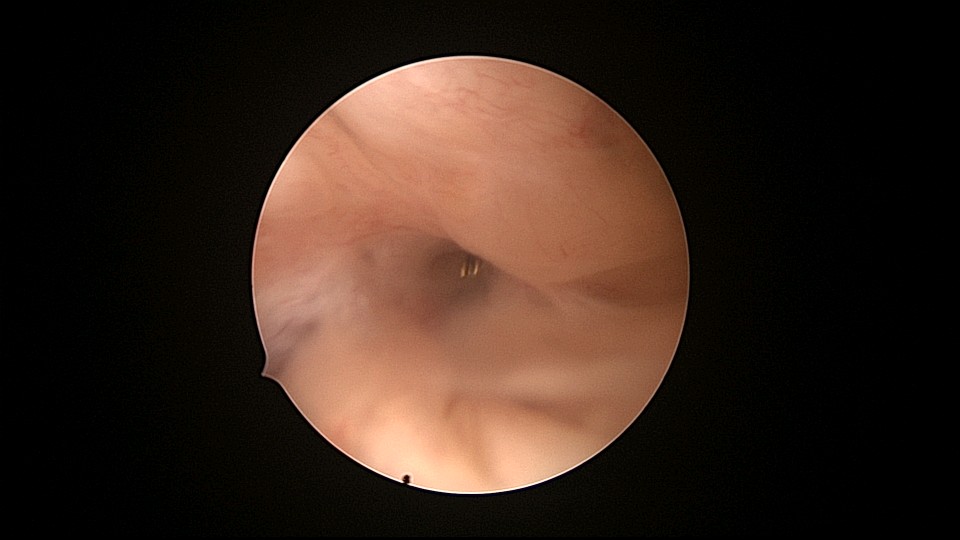

患者81岁,G5P5,顺产5次,安环50年,绝经23年,高血压病史多年,10年前因颅内肿瘤行开颅手术,4年前行腹腔镜胆囊切除术,外院介绍到我院宫腔镜取环。子宫前位,宫颈萎缩,穹隆展平,宫颈外口位于穹隆偏左侧,平滑狭小,夹持宫颈很困难,阴道内镜方式进入宫腔,见宫腔下部O型环圈内前后壁粘连,顿性分离粘连,宫腔中上部O型环与两侧宫壁嵌顿,异物钳松动节育环,但难以取出,取环钩沿镜鞘外侧进入宫腔,配合中弯钳牵拉出节育环,环变形,检查环完整,宫腔无其他异常。